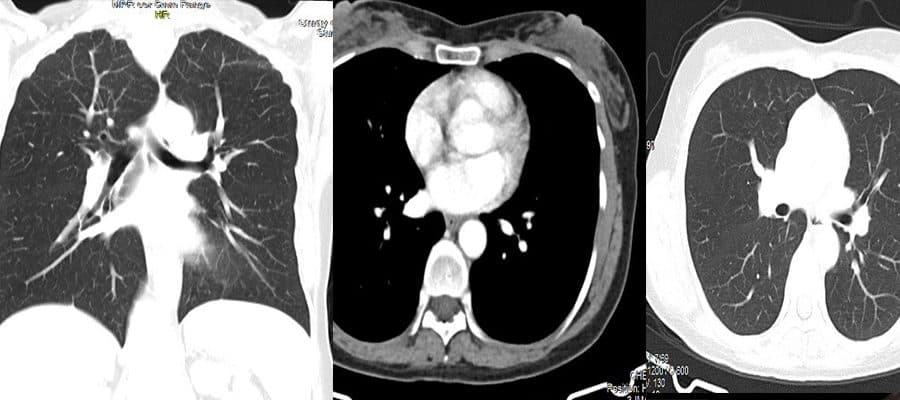

Secure your lung health with Thoracic CT! Fast and reliable results with expert radiologists. Click for MRI imaging and comprehensive check-up packages!

Examine your lungs in detail with a Thoracic CT Scan! Early diagnosis saves lives. Reliable medical imaging center. CT scan and MRI imaging services.